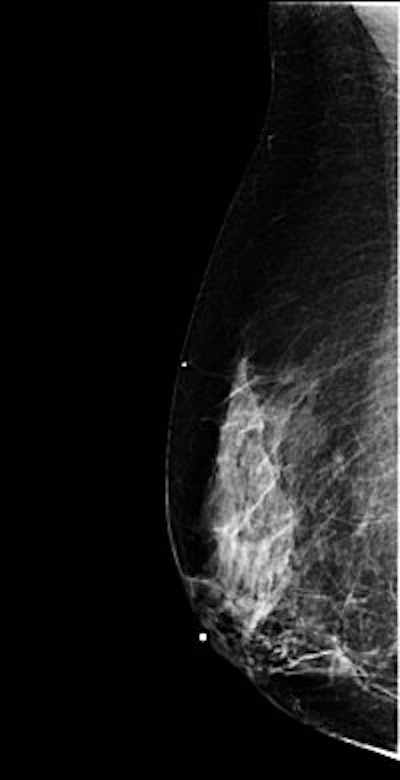

Mammography: MLO view

![]() |

| Above, right MLO ID view. Below, right MLO view with implant. Images courtesy of Tammy Coryell. |